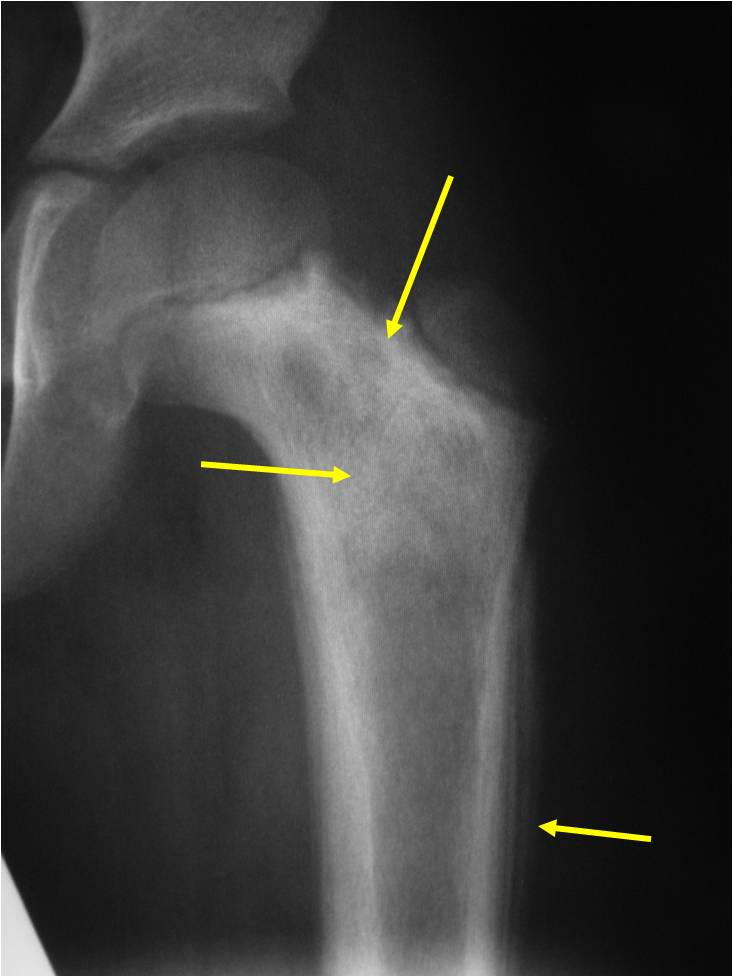

Radiographic Presentation

- Permeative or moth eaten bone destruction

- Ill defined and malignant appearing

- Bony changes are often subtle

- Soft Tissue Mass in 90% of of cases

- Periosteal Reaction in 50% of cases

- Due to irritation, edema, tumor permeation

- Onion Skin (colic pattern of irritation)

- Hair on End (rapid continuous lifting of periosteum)

- Reactive Bone Sclerosis is rare but occurs in 10% of cases

- No cartilage or bone production by tumor

- Pathologic fracture in 10-15%

- Ewing sarcoma rarely presents as a geographic, benign appearing tumor similar to a cyst or eosinophilic granuloma

- There are rare cases of periosteal ewing sarcoma with no medullary involvement